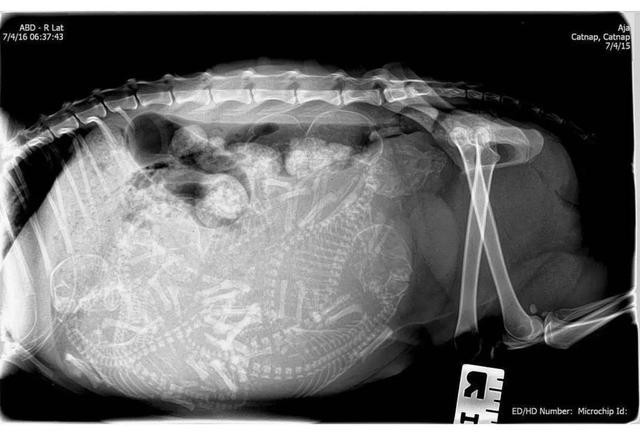

万能龙套大概有个八只

万能龙套如果奶油没有和别的狗杂交的话,这就是九只纯种的比熊犬

古修瓷Sabina老李告诉我,说一共是九只纯种的比熊犬